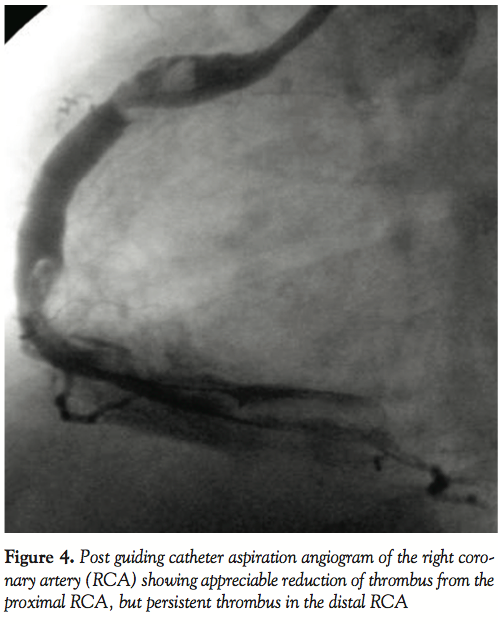

maneuvered up to the distal RCA (Figure 3). Manual suction of thrombus was then tried by attaching it to an airtight, 20 ml luer-lock syringe and gradually withdrawing it from the distal to proximal RCA. Maintaining negative suction, the guiding catheter was slowly withdrawn from the RCA and the femoral sheath. Flushing the guiding catheter outside revealed small pieces of thrombi. Angiogram following this maneuver showed appreciable reduction of the thrombus burden in the proximal RCA, but the distal RCA was still loaded with thrombus (Figure 4). The same maneuver of advancing the guiding catheter over a guidewire and Tracker catheter into the distal RCA and aspiration of thrombus was repeated. However, external flushing of the guiding catheter did not reveal any thrombi and repeat angiogram was identical to that obtained after the first aspiration. As TIMI-2 flow was achieved, we thought of tackling the residual thrombus by pharmacological means. Infusion of abciximab was continued for 12 hours. Infusion of unfractionated heparin (1,000 U/hour) was continued for 24 hours. The patient was kept under invasive hemodynamic monitoring in the coronary care unit. A check angiogram at the end of 24 hours revealed TIMI-3 flow with marked reduction of the thrombus burden in the proximal RCA and persistent large thrombus in the distal portion (Figure 5).

In the present case, we had two different anatomical factors that complicated the situation. First, the RCA was diffusely ectatic. Second, the thrombus burden was huge, extending from proximal to distal. To date, no definite data are available concerning the optimal strategy to be adopted when the thrombus burden is so large. In such conditions, because of the risk of no reflow associated with PTCA, antithrombotic medical modalities have a significant adjunctive role to PTCA.5 In this case, since the artery was totally occluded and the patient was having CCS class III angina, we decided to open up the artery by balloon angioplasty. Following angioplasty with a 2.5 mm balloon, angiogram revealed a large ectatic RCA with TIMI-1 flow and a large thrombus burden; therefore, we thought of reducing the thrombus burden mechanically. As the X-sizer device was not successful in debulking, aspiration of the thrombus by a 7 Fr guiding catheter was contemplated. Though guiding catheter aspiration of thrombus from native coronary arteries and venous grafts has previously been reported,6–8 the technique involves the risk of inducing dissection and systemic thrombo embolism. To minimize this risk, we adopted a novel strategy of passing the catheter over a 3 Fr Tracker catheter. Deep intubation of the guiding catheter over wire alone is often difficult. Even this required careful manipulation of the guiding catheter over the wire and the tracker catheter. Though only a portion of thrombus could be removed mechanically, stopping further debulking judiciously once TIMI-2 flow was achieved, switching over to pharmacological means (infusion of abciximab for 12 hours and heparin for 24 hours) for further reduction of the thrombus burden led TIMI-3 flow.